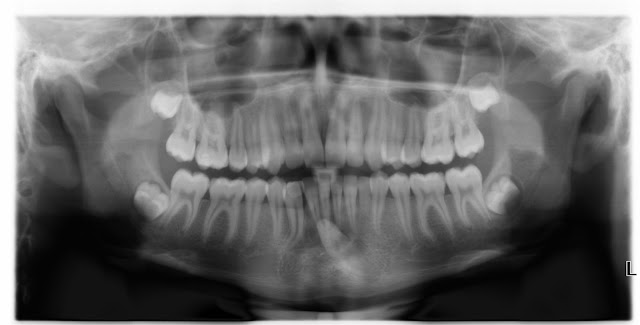

En ny pasient med et stort kariesangrep ble lovet den nye, og banebrytende behandlingen med BIOENTIN for å prøve å unngå rotfylling. Biodentinet ble meget insisterende solg inn av tannlegen med stor tro på materialet.

Kariesangrepet ble eskavert, og det var ganske riktig en liten perf der. Matrisen ble montert, og da viste det seg at folieposen med Biodentinvæsken var TOM!